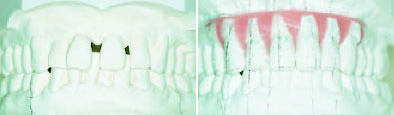

Ealsto-Finisher: Finisher берет на себя трудную задачу: точную доводку в конце лечения

Традиционные позиционеры утратили свою первоначальную задачу закрытия трем между зубами после снятия колец, т.к. брекеты, фиксируемые на зубах без колец, не оставляют после себя трем. Но заключительный этап лечения несъемными аппаратами зачастую более трудоёмок, чем предваряющие ему большие перемещения зубов на этапах нивелирования и выравнивания (рис. 1-3).

Рис.1: К окончанию лечения бугрово-фиссурные контакты не достигнуты.

Elasto-Finisher изготавливается из высокоэластичного Silasto 50. Этот материал отличается особо высокой прочностью на растяжение и при деформациях. Такие благоприятные характеристики имеют только силиконы, вулканизированные при высоких температурах.

Рис.2: Set-up визуализирует цель лечения.

Вертикальное перемещение клыков, достижение их смыкания по 1 классу, а также восстановление направляющей функции клыков, как фактор долговременной стабильности результата, составляют значительную часть времени лечения. Нетерпеливые пациенты зачастую недопонимают этого.

В отличие от лечения с помощью обычного позиционера, который изготавливается после демонтажа несъемного аппарата, при использовании Elasto-F inisher на зубах остаются брэкеты и кольца на молярах. До изготовления матрицы для дублирования моделей снимают только ортодонтические дуги и лигатуру, поскольку они не должны быть вплавлены в Elasto-Finisher. Достаточно заблокировать весь ряд зубов с помощью непрерывной лигатуры в виде восьмерки.

Рис.3: Брекеты и кольца были сняты спустя 10 недель, но пациент продолжал носить аппарат по ночам в течение одного года.